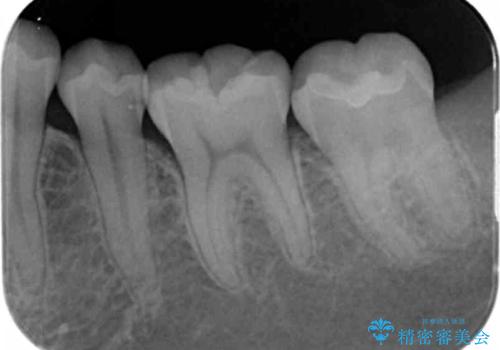

- 下の奥歯の黒ずみが気になるとのことで来院されました。

検査の結果咬む面に虫歯があることがわかりました。

- 左下7 セラミックインレー 77,000円費用は治療当時の料金となります

削る前は小さな虫歯に見えますが、歯の中で進行しつつある虫歯でした。

虫歯が大きくなると必要な治療が増えてえしまうため早期発見、早期治療を行うことが大事になってきます。